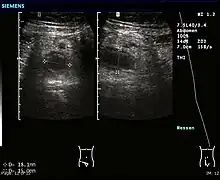

Ultrasound

Abdominal ultrasonography, preferably with doppler sonography, is useful to detect appendicitis, especially in children. Ultrasound can show the free fluid collection in the right iliac fossa, along with a visible appendix with increased blood flow when using color Doppler, and noncompressibility of the appendix, as it is essentially a walled-off abscess. Other secondary sonographic signs of acute appendicitis include the presence of echogenic mesenteric fat surrounding the appendix and the acoustic shadowing of an appendicolith.[59] In some cases (approximately 5%),[60] ultrasonography of the iliac fossa does not reveal any abnormalities despite the presence of appendicitis. This false-negative finding is especially true of early appendicitis before the appendix has become significantly distended. Also, false-negative findings are more common in adults where larger amounts of fat and bowel gas make visualizing the appendix technically difficult. Despite these limitations, sonographic imaging with experienced hands can often distinguish between appendicitis and other diseases with similar symptoms. Some of these conditions include inflammation of lymph nodes near the appendix or pain originating from other pelvic organs such as the ovaries or Fallopian tubes. Ultrasounds may be either done by the radiology department or by the emergency physician.[61]